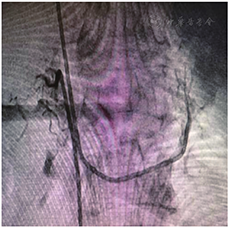

为进一步明确有无醛固酮优势分泌,充分与患者及家属沟通后行双侧肾上腺动脉采血(图2),结果见表1。经计算,左侧选择指数3.6,右侧选择指数36.3,提示分侧采血成功。优势指数4.77,对侧抑制指数0.22。提示肾上腺分泌醛固酮左侧优势型明显。